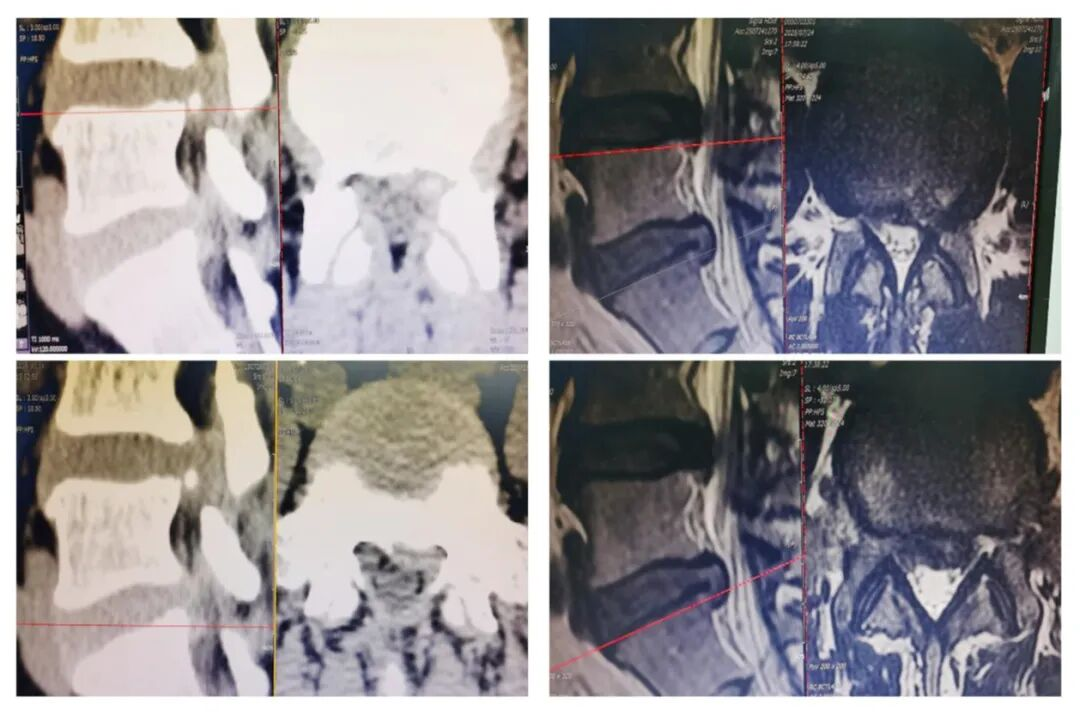

▲(术前)腰椎MRI示:腰5/骶1椎间盘膨出并突出,并椎管继发轻度狭窄,腰4/5椎间盘膨出

患者入院后做了详细的体格检查,结合患者病史、症状、体征及辅助检查,确诊为腰5/骶1椎间盘突出并椎管狭窄,治疗方案方面,医生与患者及家属做了详细的沟通,患者考虑到保守治疗效果不明显,且症状已经难以忍受,严重影响了日常起居生活,经慎重考虑后决定手术治疗。